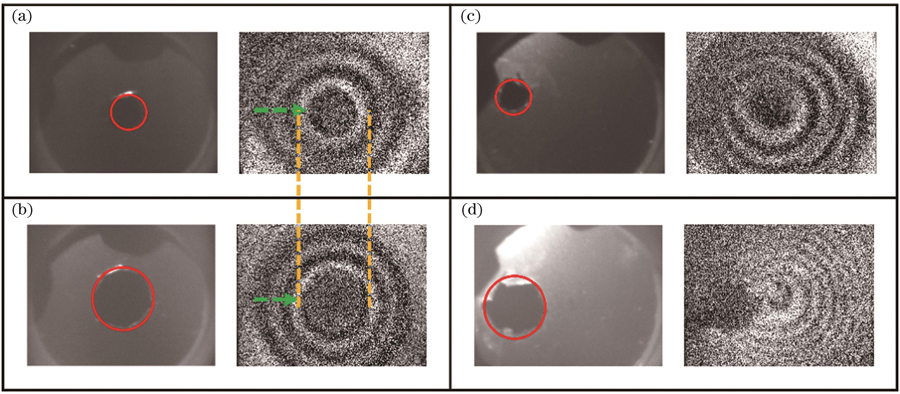

针对上述的薄膜划伤仿真分析,同样进行了相应的实验验证,得到的中心划痕样本的一阶振动模态图如

图 12. 划伤薄膜的一阶振动模态图。(a)中心3 mm划伤薄膜;(b)中心6 mm划伤薄膜;(c)偏心3 mm划伤薄膜;(d)偏心6 mm划伤薄膜

Fig. 12. First-order vibrational mode diagrams of scratched films. (a) Film with a 3 mm scratch in the center; (b) film with a 6 mm scratch in the center; (c) film with an eccentric 3 mm scratch; (d) film with an eccentric 6 mm scratch